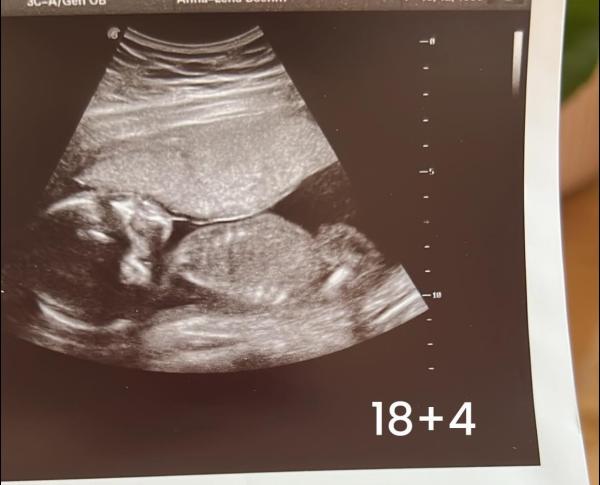

Beim Ultraschall bei 18+4 sagte sie Tendenz zum Mädchen.heute wieder zum Ultraschall gewesen und ich weiß immer noch kein Geschlecht erst meinte sie heute junge dann ne halt stopp da sind schamlippen Mädchen dann sagte sie sind sie sich sicher Mädchen wird es. Und ganz am Schluss ne stop kann doch ein Junge sein und Schluss endlich sagte sie tut mir leid kann ich ihnen nicht sagen. Ich bin bei 28+3 und das war der letzte Ultraschall vor der Geburt. Ja ich weiß das es nicht überall so ist mit dem Ultraschall diese Diskussionen bitte ich auch garnicht zu eröffnen. Ebenso weiß ich auch das es die Hauptsache es das es gesund ist aber man würde es ja schon gerne wissen. Hat jemand ne Idee oder so wie man es noch rausfinden kann? Das Bild habe ich grade in meinem Mutterpass gefunden. Sie sagte kann schammlippen sein kann auch ein Pennis sein und das das alles noch recht gleich aussehen kann. Und auch Mädchen unten einen Zipfel haben können auf Ultraschall Bildern 🤷🏼♀️ Durch blutest das Geschlecht bestimmen geht nicht mehr sagt die Frauenärztin 🤷🏼♀️ Ebenso viel das Wort geschwollen Klitoris. Und ne Freundin meinte das auch die Nabelschnur zwischen den Beinen sein könnte Weil das Stück was da raus guckt sage ich mal recht groß ist und weit nach hinten geht wenn man ganz genau schaut, ich hab das mal mit einem roten Strich markiert

Also nach acht Kindern ( 5 Mädels und drei Jungs) sieht das letzte Bild schon sehr nach Junge aus und nix nach Schamlippen oder geschwollener Klitoris. Was du noch machen kannst wäre zu einem Pränataldiagnostiker gehen ( degum2 oder degum 3) allerdings wirst du das selber bezahlen müssen und die sind oft auf Wochen ausgebucht weil die eigentlich halt bei Auffälligkeiten schallen